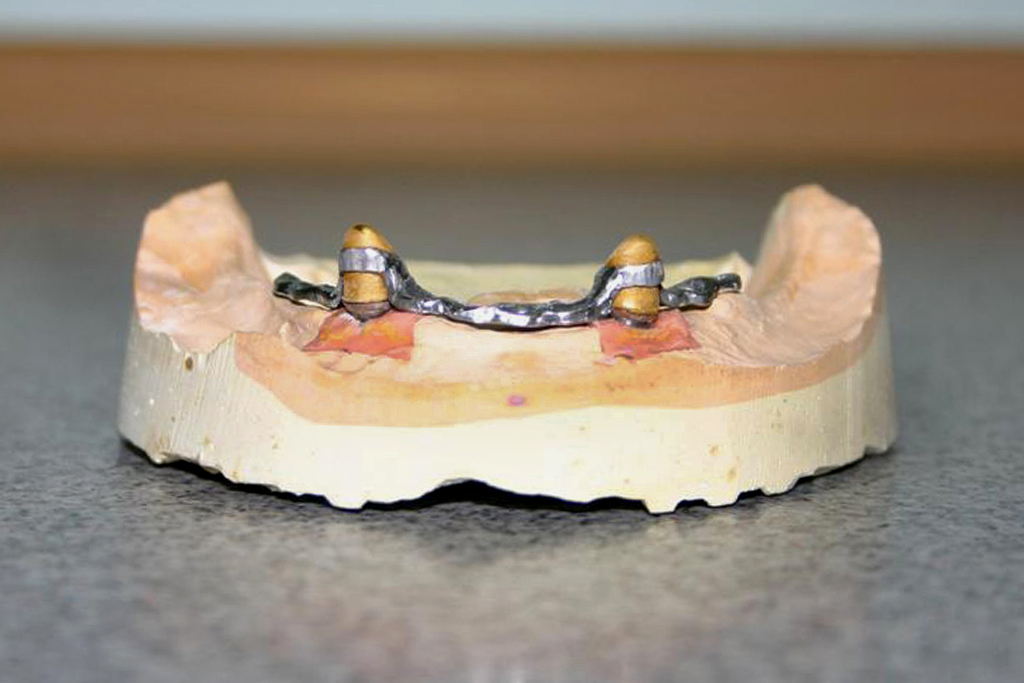

VIII. Proteza szkieletowa dolna osadzona na implantach i koronach teleskopowych

1. Pacjent z założonymi śrubami zaślepiającymi na implantach

2. Etap laboratoryjny - łączniki implantów na modelu gipsowym, na którym będzie projektowana proteza szkieletowa osadzona na dwóch koronach teleskopowych

3. Etap laboratoryjny -gotowy szkielet metalowy protezy z dwoma koronami teleskopowymi na modelu gipsowym

4.Przymiarka szkieletu protezy z koronami teleskopowymi w ustach pacjenta